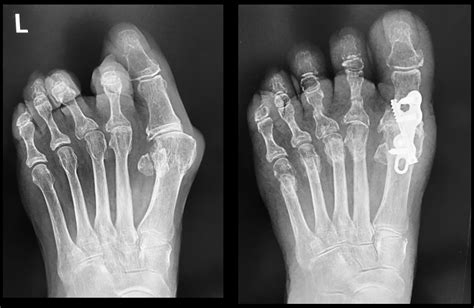

When conservative methods fail to provide adequate relief, or if the arthritis in big toe significantly impairs daily functioning, surgical intervention may be recommended. The type of surgery depends on the severity of the damage, the patient's age, and their activity level.

• Cheilectomy: This involves removing the bone spurs from the top of the joint, which can improve range of motion and reduce impingement.

• Osteotomy: A procedure to cut and realign the metatarsal bone to offload the pressure on the damaged joint.

• Arthrodesis (Fusion): This is considered the "gold standard" for advanced cases. The two bones forming the MTP joint are fused together. While this eliminates motion in the joint, it also eliminates the pain, allowing for a normal walking gait.